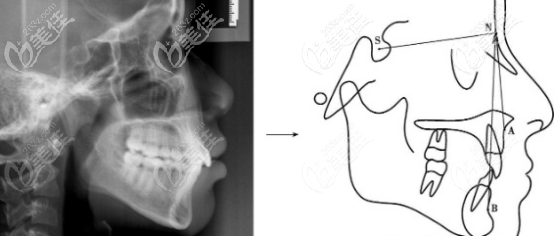

你知道做下颌角切除手术前要进行3项体检还要拍片吗?

下颌角切除手术可被划分为3级整形手术,所以术前一定要认真对待,医院会给你进行两项体检,还要拍片设计方案。